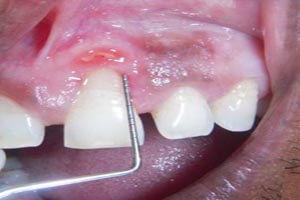

The pyogenic granuloma is a relatively common, tumorlike, exuberant tissue response to localized irritation or trauma. The name pyogenic granuloma is a misnomer since the condition is not associated with pus and does not represent a granuloma histologically. It is a reactive inflammatory process filled with proliferating vascular channels, immature fibroblastic connective tissue, and scattered inflammatory cells. The surface usually is ulcerated, and the lesion exhibits a lobular architecture.

After